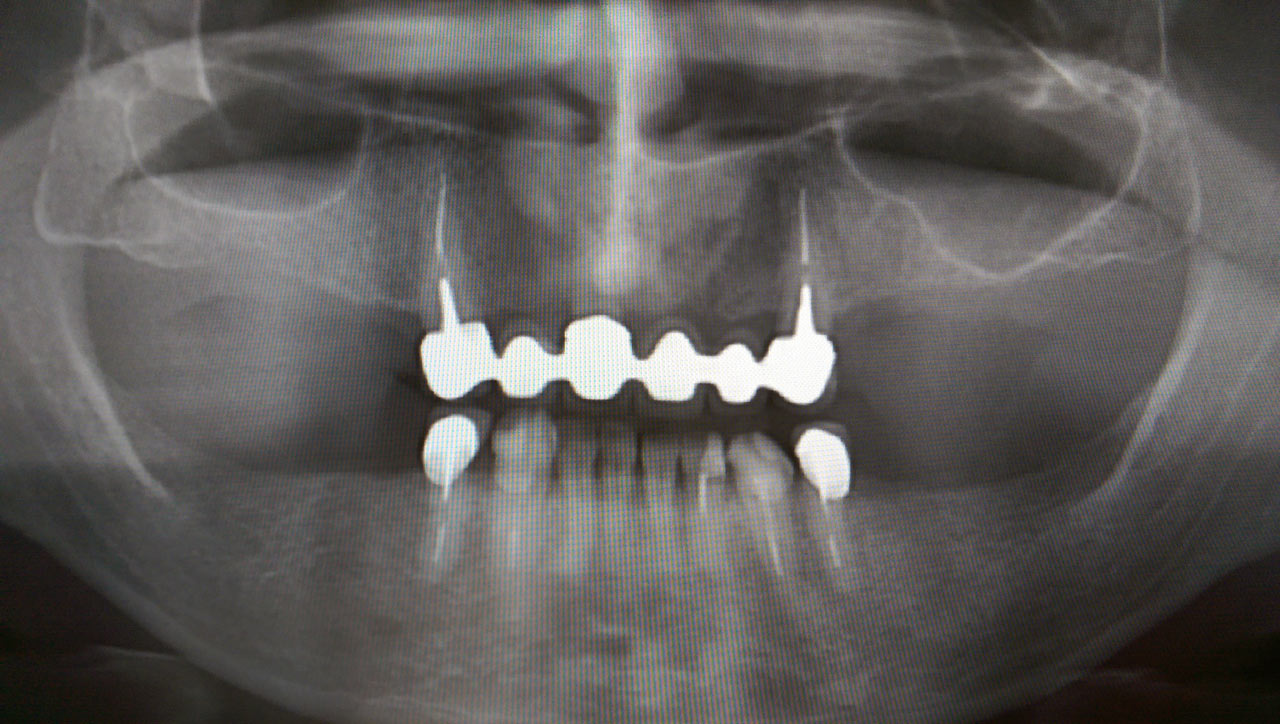

Teljes fogatlanság helyreállítása 2 nap alatt

Teljes fogatlanság helyreállítása 2 nap alatt azonnal terhelhető svájci IHDE implantátumokkal és PMMA műanyag hidakkal. Intraorális szkennerrel vettünk lenyomatot az implantáció után, és erre a digitális mintára készítette el a fogtechnika a hidak digitális tervezését, majd faragta ki műanyagból. Ezt a gyors munkát az azonnal terhelhető implantátumok és a digitális lenyomat, tervezés segítségével tudtuk megcsinálni mindössze 2 nap alatt. Dr. Kelemen Péter és a Symbion Fogtechnika munkája.